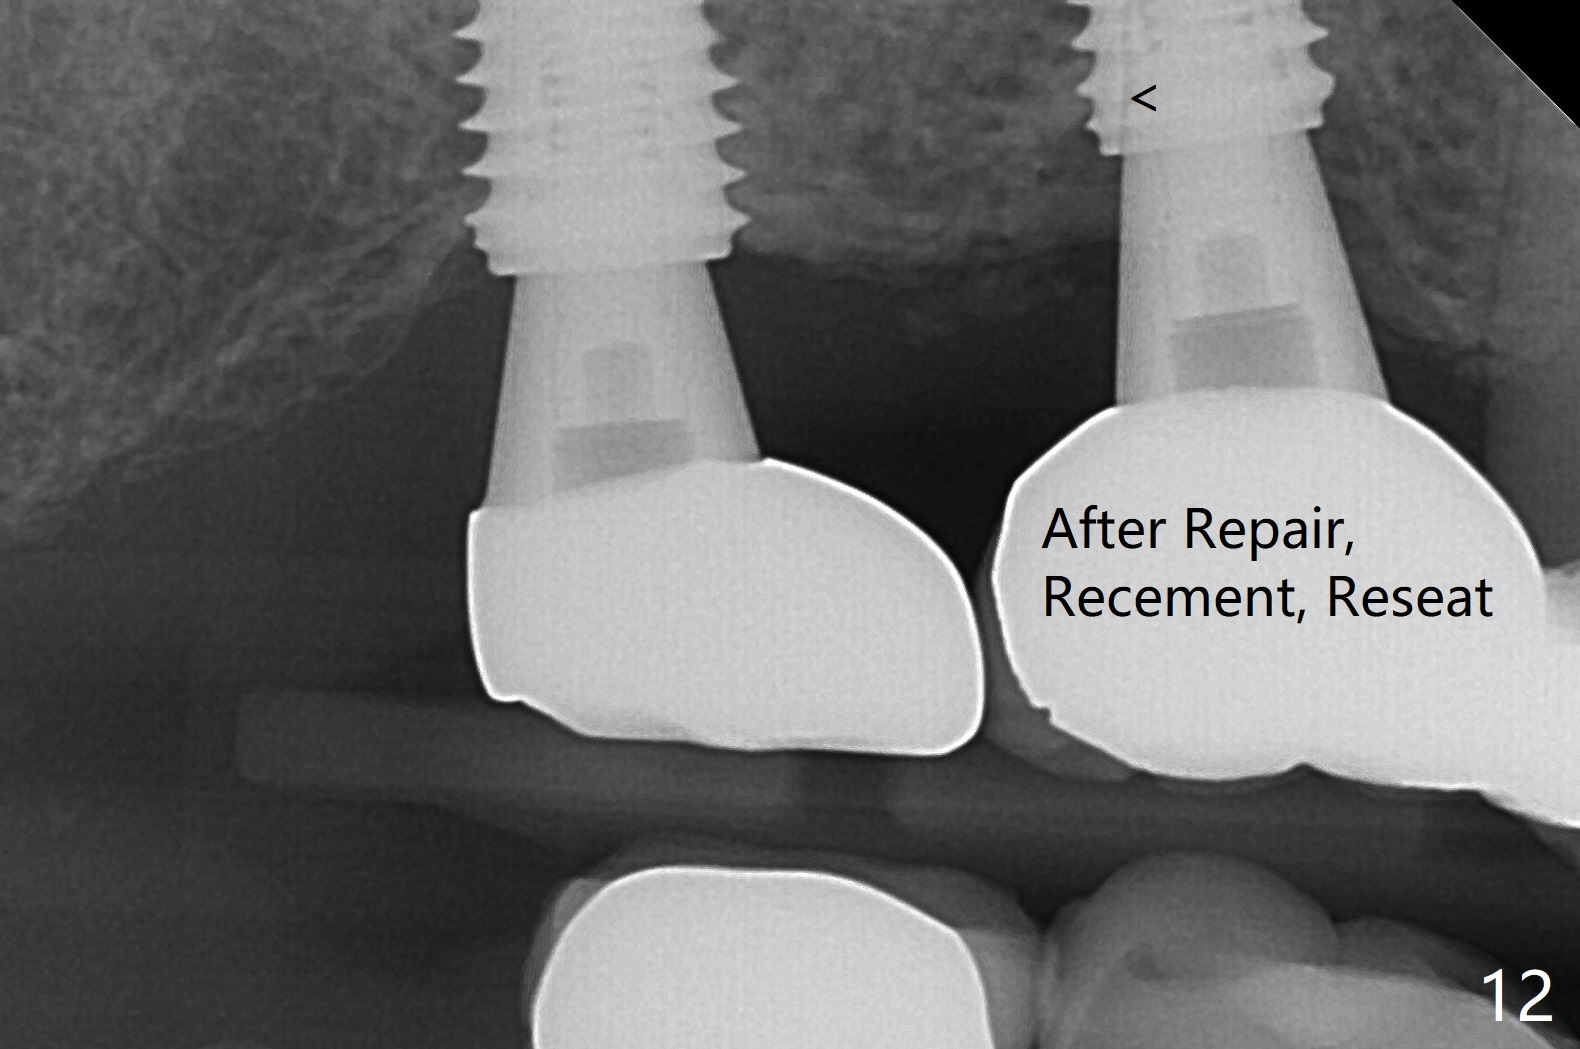

Osteotomy at the sites of #2 and 3 goes on as planned. Sinus lift using DIO 2.8 mm round bur with 6 and 7 mm stoppers (respectively) is carried on without certainty, because it is difficult to feel the stop through the osteotomy. The crest may be uneven or soft. It appears that the soft tissue landmark as a stop may be easier to identify. In fact a 3 mm IBS Magic Expander (an osteotome) was used for sinus lift at #3. The 2 implants are placed with 20 and 30 Ncm (Fig.1,2). Healing abutments are inserted. At 2-week follow-up, the patient reports "pain a few days earlier, took a pill of antibiotic, pain gone. UR metal is sharp". She does not take antibiotic regularly. Exam reveals that there is heavy plaque around #2,3 healing abutments. The buccal edge of #2 abutment is trimmed for comfort. Nearly 1 month postop, #3 healing abutment dislodges with buccal gingival erythema and edema with purulent discharge (Fig.3). Healing screw is placed at #3 with Amoxicillin and Chlorhexidine prescribed. One week later, the implant at #3 turns when the healing screw is retightened (Fig.4). After debridement, Vanilla graft is placed. There is no infection at #2 or 3 four months postop (Fig.5,6); the lingual gingiva is erythematous and edematous at #29 with mobility II (Fig.7 (vertical root fracture)). Uncover is conducted at the site of #3; there is no infection superficial 7.5 months postop (Fig.8). There is a large buccal defect upon incision with dark hemorrhage. In fact the bone density is low crestally (Fig.8 *). Bone graft is placed for the 2nd time. Eleven months later (1.5 years post implant placement), the bone regrows crestal (Fig.9 *). The crown at #3 is loose 1 year 5 months post cementation (Fig.10). After proximal trimming (Fig.11 *), the abutment at #3 is seated completely. After lab repair, crown oral cement, crown/abutment removal for excess cement removal, the crown/abutment cannot be torqued >25 Ncm (Fig.12, 30 Ncm). PA shows incomplete seating (Fig.12 <). Then the crown is sectioned so that the abutment has more freedom to be seated completely with pressure against the gingiva (the patient feels pain, Fig.13). Torque is 30 Ncm. After crown cementation, the abutment will not be removed for cement removal.